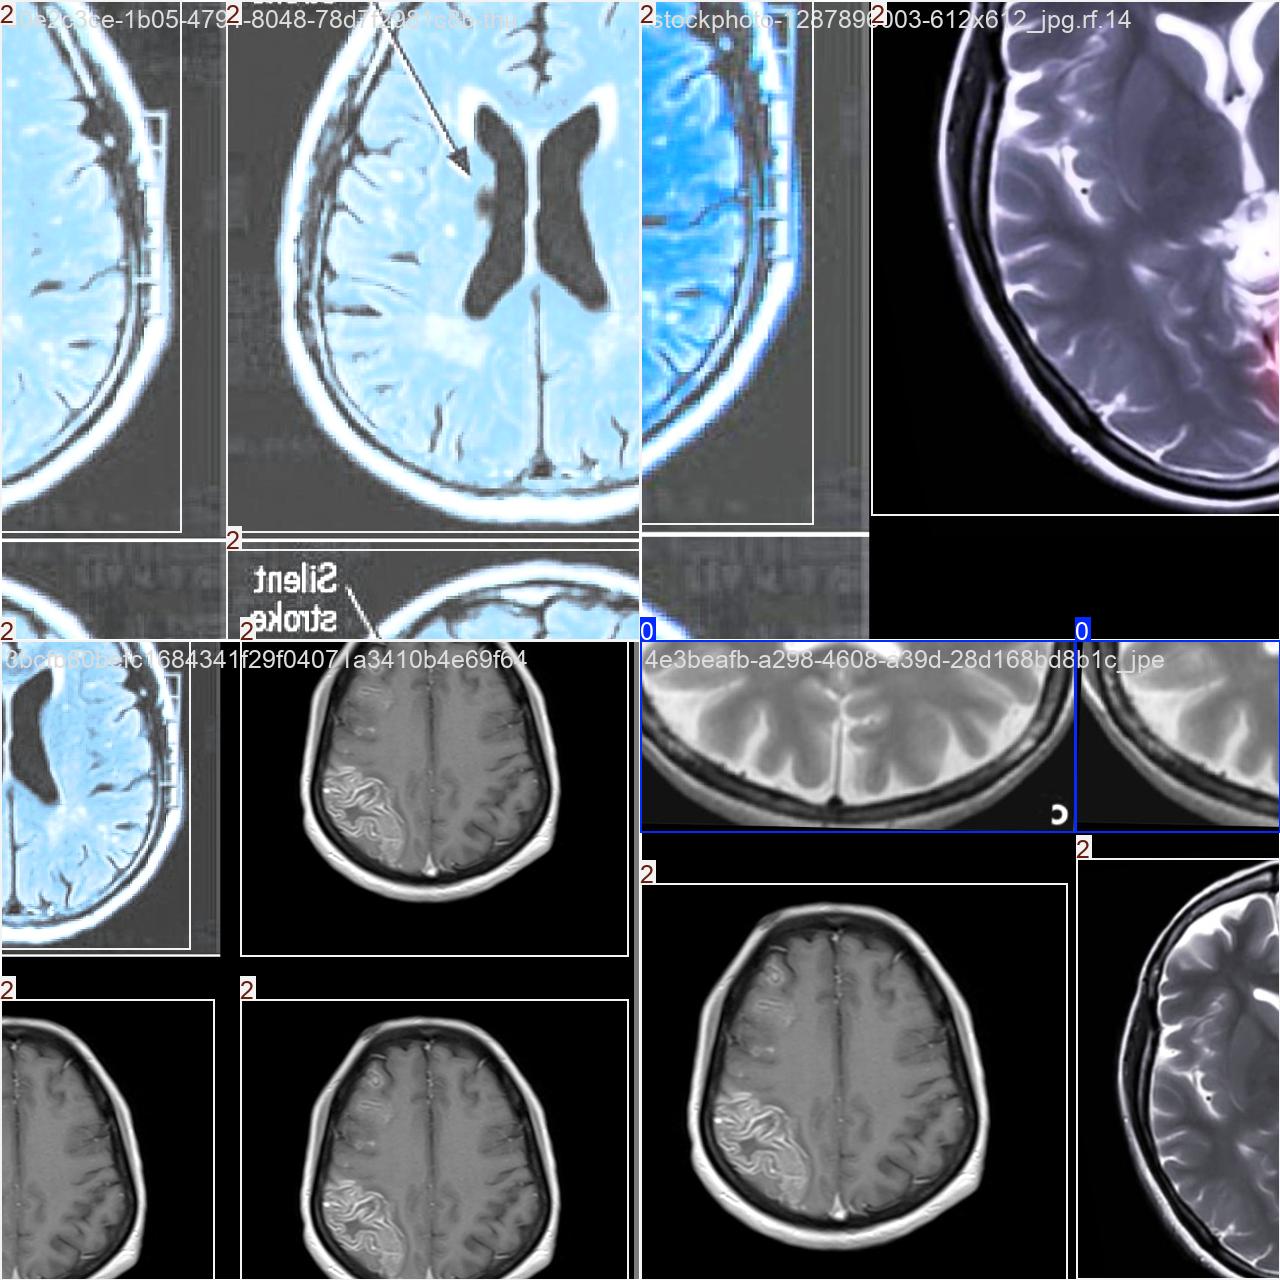

该数据集用于脑部疾病(癫痫、脑中风)目标检测任务。

类别:3类 [‘癫痫性脑部疾病’, ‘脑中风性脑部疾病’, ‘脑部功能正常’]

标签(names): [‘Epilepsy’, ‘Healthy’, ‘Stroke’]

目标检测训练数据可视化

目标检测训练过程中,模型对数据的可视化结果,主要展示了多个类别目标的检测边框和类别标注情况。整体检测表现较好,但可以通过优化标注和模型训练进一步提升精度和鲁棒性。